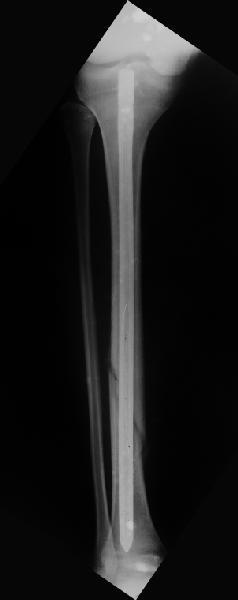

Дорогой Александр. Имею скромный опыт использования системы Fixion при переломах плеча, бедра и тибии. Всего 18 наблюдений с сентября 2006 г. Результаты отличные. Гвоздь индивидуален для каждого медуллярного канала. Легко имплантируется как в узкий, так и в деформированный канал. Это позволяет применять метод интрамедулярного остеосинтеза без ненужных потерь времени операции, флюороскопии и реально снижает крвопотерю и операционный риск. Удаление происходит без проблем. Особенно интересны больные с ипсилатеральными переломами бедра и голени.

В отношении ранней нагрузки при спиральных переломах лучше не торопиться. По данному случаю необходимо достигнуть исчезновения щели между штифтом и внутреним кортексом по Rg. А так картинка прекрасная - и длина сегмента и репозиция. Можно поздравить, коллега!